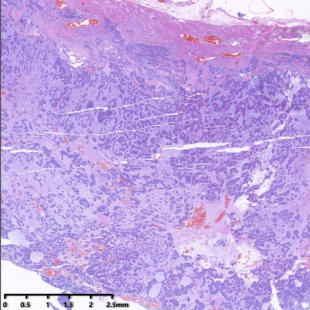

低倍镜下肿物具有厚的纤维包膜,肿瘤由实性巢状结构、假乳头结构及出血区域组成,部分区域间质黏液变性。实性区呈片状或大小不一的巢状,假乳头状区为分枝状乳头,含纤维血管轴心,乳头表面细胞黏附性较差,脱落。肿瘤细胞形态温和,大小一致,核圆形或卵圆形,核染色质细腻,轻度异型性,核分裂少见,无肿瘤性坏死。

低倍镜,肿瘤具有厚的纤维性包膜及多样的组织学结构,由实性巢状区域、假乳头区域及出血区域组成,间质黏液变性,部分区域囊性变。

中倍镜,实性区域呈实性片状或大小不一的巢状,假乳头状区为分枝状乳头,乳头表面细胞黏附性较差,脱落明显。

肿瘤具有厚薄不一的纤维性包膜及多样的组织学结构,由实性区域(最常见)、囊性区域、假乳头区域、退变区域及出血区域按照不同比例混合而成,间质常伴有黏液变性。实性区域呈实性片状、大小不一的实性巢状。囊性区域常有内部肿瘤细胞退变脱落后形成,囊腔大小不等。假乳头状区为分支状乳头,含纤维血管轴心,乳头表面被覆数层肿瘤细胞,细胞黏附性较差,细胞脱落。肿瘤细胞形态大小较一致,胞质丰富嗜伊红,细胞核卵圆形,部分可见核沟,无明显核仁,核分裂象罕见,其形态类似神经内分泌肿瘤细胞。少数病例可伴有高级别转化,高级别区域细胞核分裂易见,Ki-67增殖指数高。